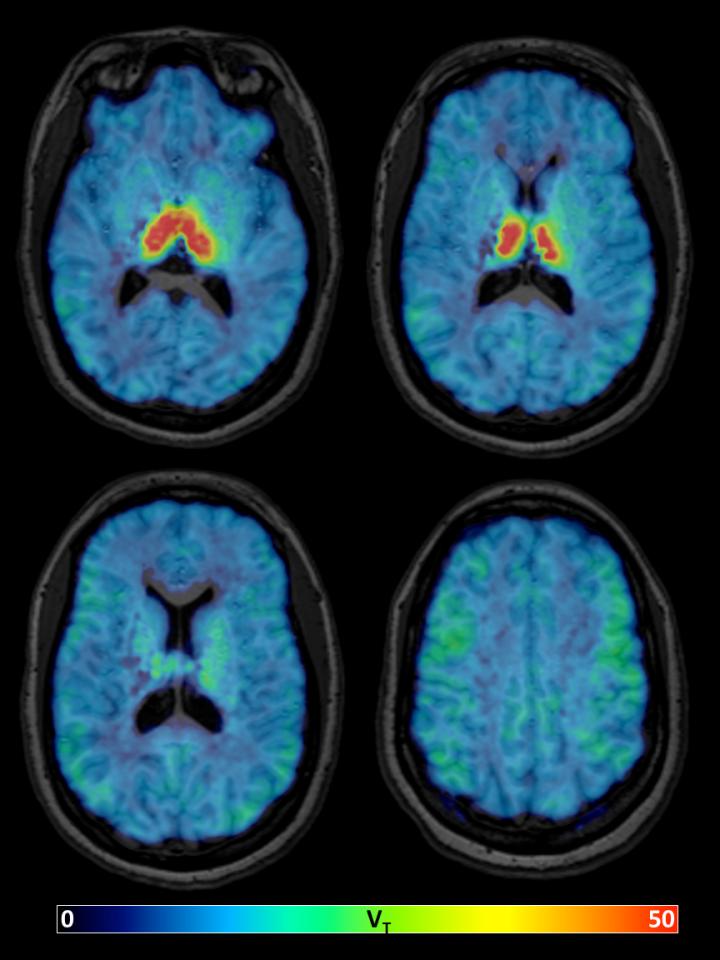

RESTON, VA - A new PET imaging radiotracer could help researchers understand neurodegenerative disease and the aging brain. The study is featured in the October issue of The Journal of Nuclear Medicine .

A team at Johns Hopkins University assessed the pharmacokinetic behavior of 18 F-XTRA, a new PET imaging radiotracer for the α4β2-nAChR. The researchers tested the new radiotracer on a group of 17 adults and focused on extrathalamic regions of the brain. The research team found that 18 F-XTRA rapidly entered the brain and distributed quickly.

"We present data using a new radiotracer with PET to characterize the distribution of the α4β2-nAChR in the human brain," said Martin Pomper, MD, PhD. "The observed high uptake into the brain, fast pharmacokinetics, and ability to estimate binding in extrathalamic regions within a 90-minute scan supports further use of 18 F-XTRA in clinical research populations. We also report the finding of lower 18 F-XTRA binding in the hippocampus with healthy aging, which marks a potentially important finding from biological and methodological perspectives."

"Together, our results suggest that 18 F-XTRA PET may be sufficiently sensitive to measure the hypothesized loss of α4β2-nAChR availability over aging, particularly in the hippocampus," Dr. Pomper said. "This is a promising tool for the future study of changed cholinergic signaling in the brain over healthy aging that may be linked to changes in memory over the lifespan."